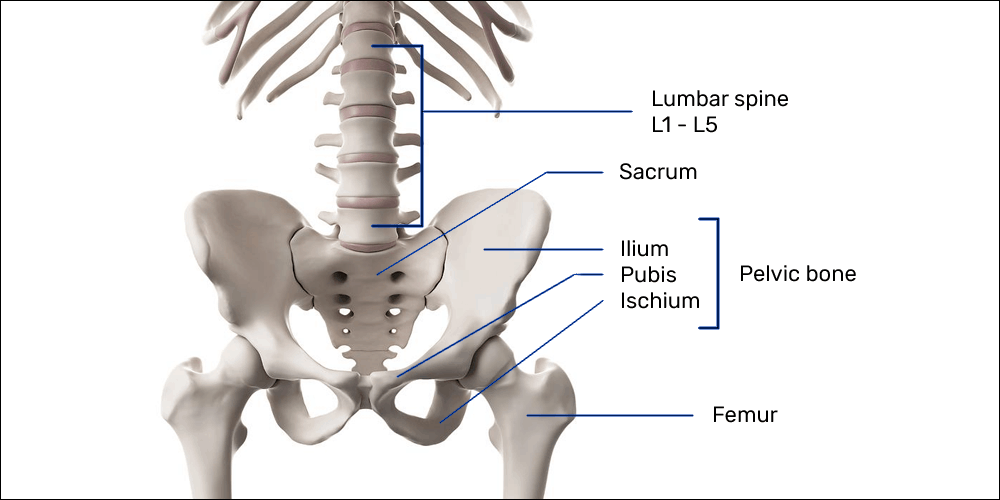

Структура позвоночника: сегменты и тазовые отделы в фотографиях